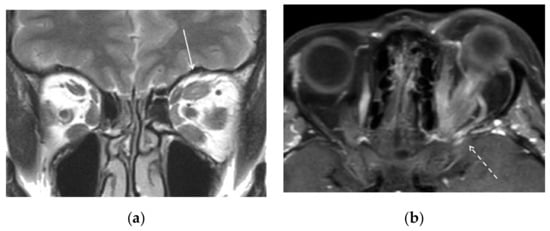

A transvenous approach was then attempted. The procedure was performed, under general anesthesia, through a venous and arterial femoral access. A full dose of 5.000 UI of intravenous unfractionated heparin (sodium heparin) was administered at the beginning of the procedure. On the venous side, we used a guiding catheter with the distal tip at the left jugular bulb. On the arterial side, we used a diagnostic catheter with the distal tip in the left maxillary artery for diagnostic purpose. From the venous side, we attempted with microcatheter and microguidewires to access the left inferior or left superior petrosal sinus to retrogradely access the diseased portion of the CS and occlude it with coils with a technique that has previously been described and is generally associated with high rates of success [8,9]. Nevertheless, despite several attempts, we could not negotiate the venous pouch (Figure 4a,b).

Figure 4. DSA. Embolization procedure. Left common carotid artery, lateral view. (a) Left inferior (arrow) and (b) left superior petrosal sinus (small arrows) catheterization. No access to the venous pouch of the fistula could be found.